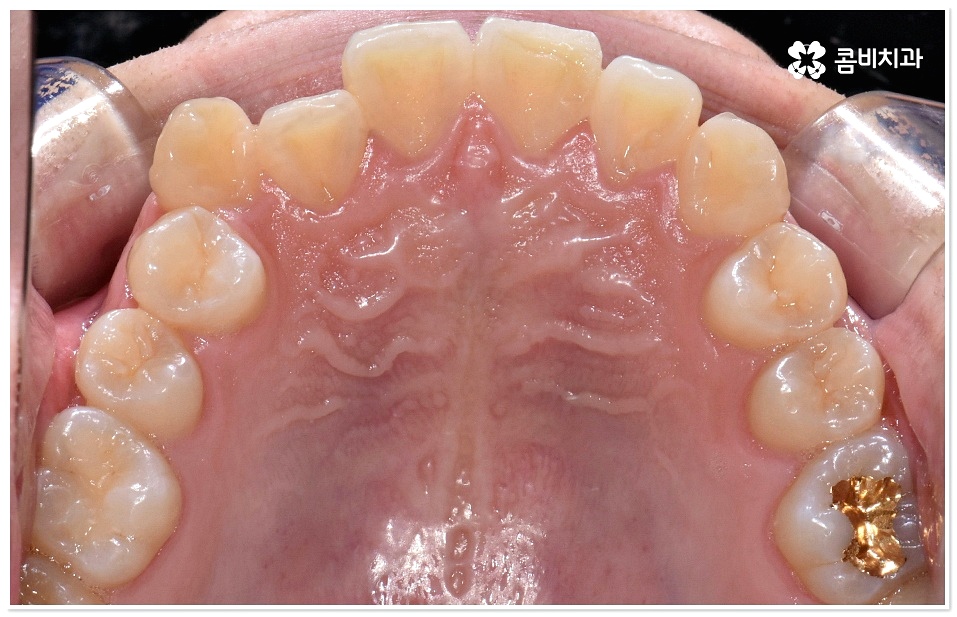

교정 치료란 특수한 장치를 이용해 치아를 원하는 방향으로 이동시켜 치아 배열과 교합을 올바르게 개선해 주는 과정으로 각자의 구강 구조가 다 다르기 때문에 정밀 검사를 통해 환자분들 각각의 치아 모양과 각도, 위치, 교합 뿐 아니라 잇몸 건강 상태 및 상악과 하악의 관계와 같은 구강 내 상황과 함께 입술, 전체 안모 등 대칭과 균형의 측면에서 모든 부분을 다각적이고 입체적으로 분석한 후 세밀한 맞춤 계획을 수립하는 것이 중요할 수 있는데요.

그러므로 3D CT와 같은 정밀 검진 장비와 3D 모르페우스와 같은 시스템을 갖추고 다양한 경험과 노하우를 바탕으로 정확한 진단 및 섬세한 플랜을 세울 수 있는 치과를 잘 알아보고 덧니치아교정 치료를 진행하실 필요가 있어요.